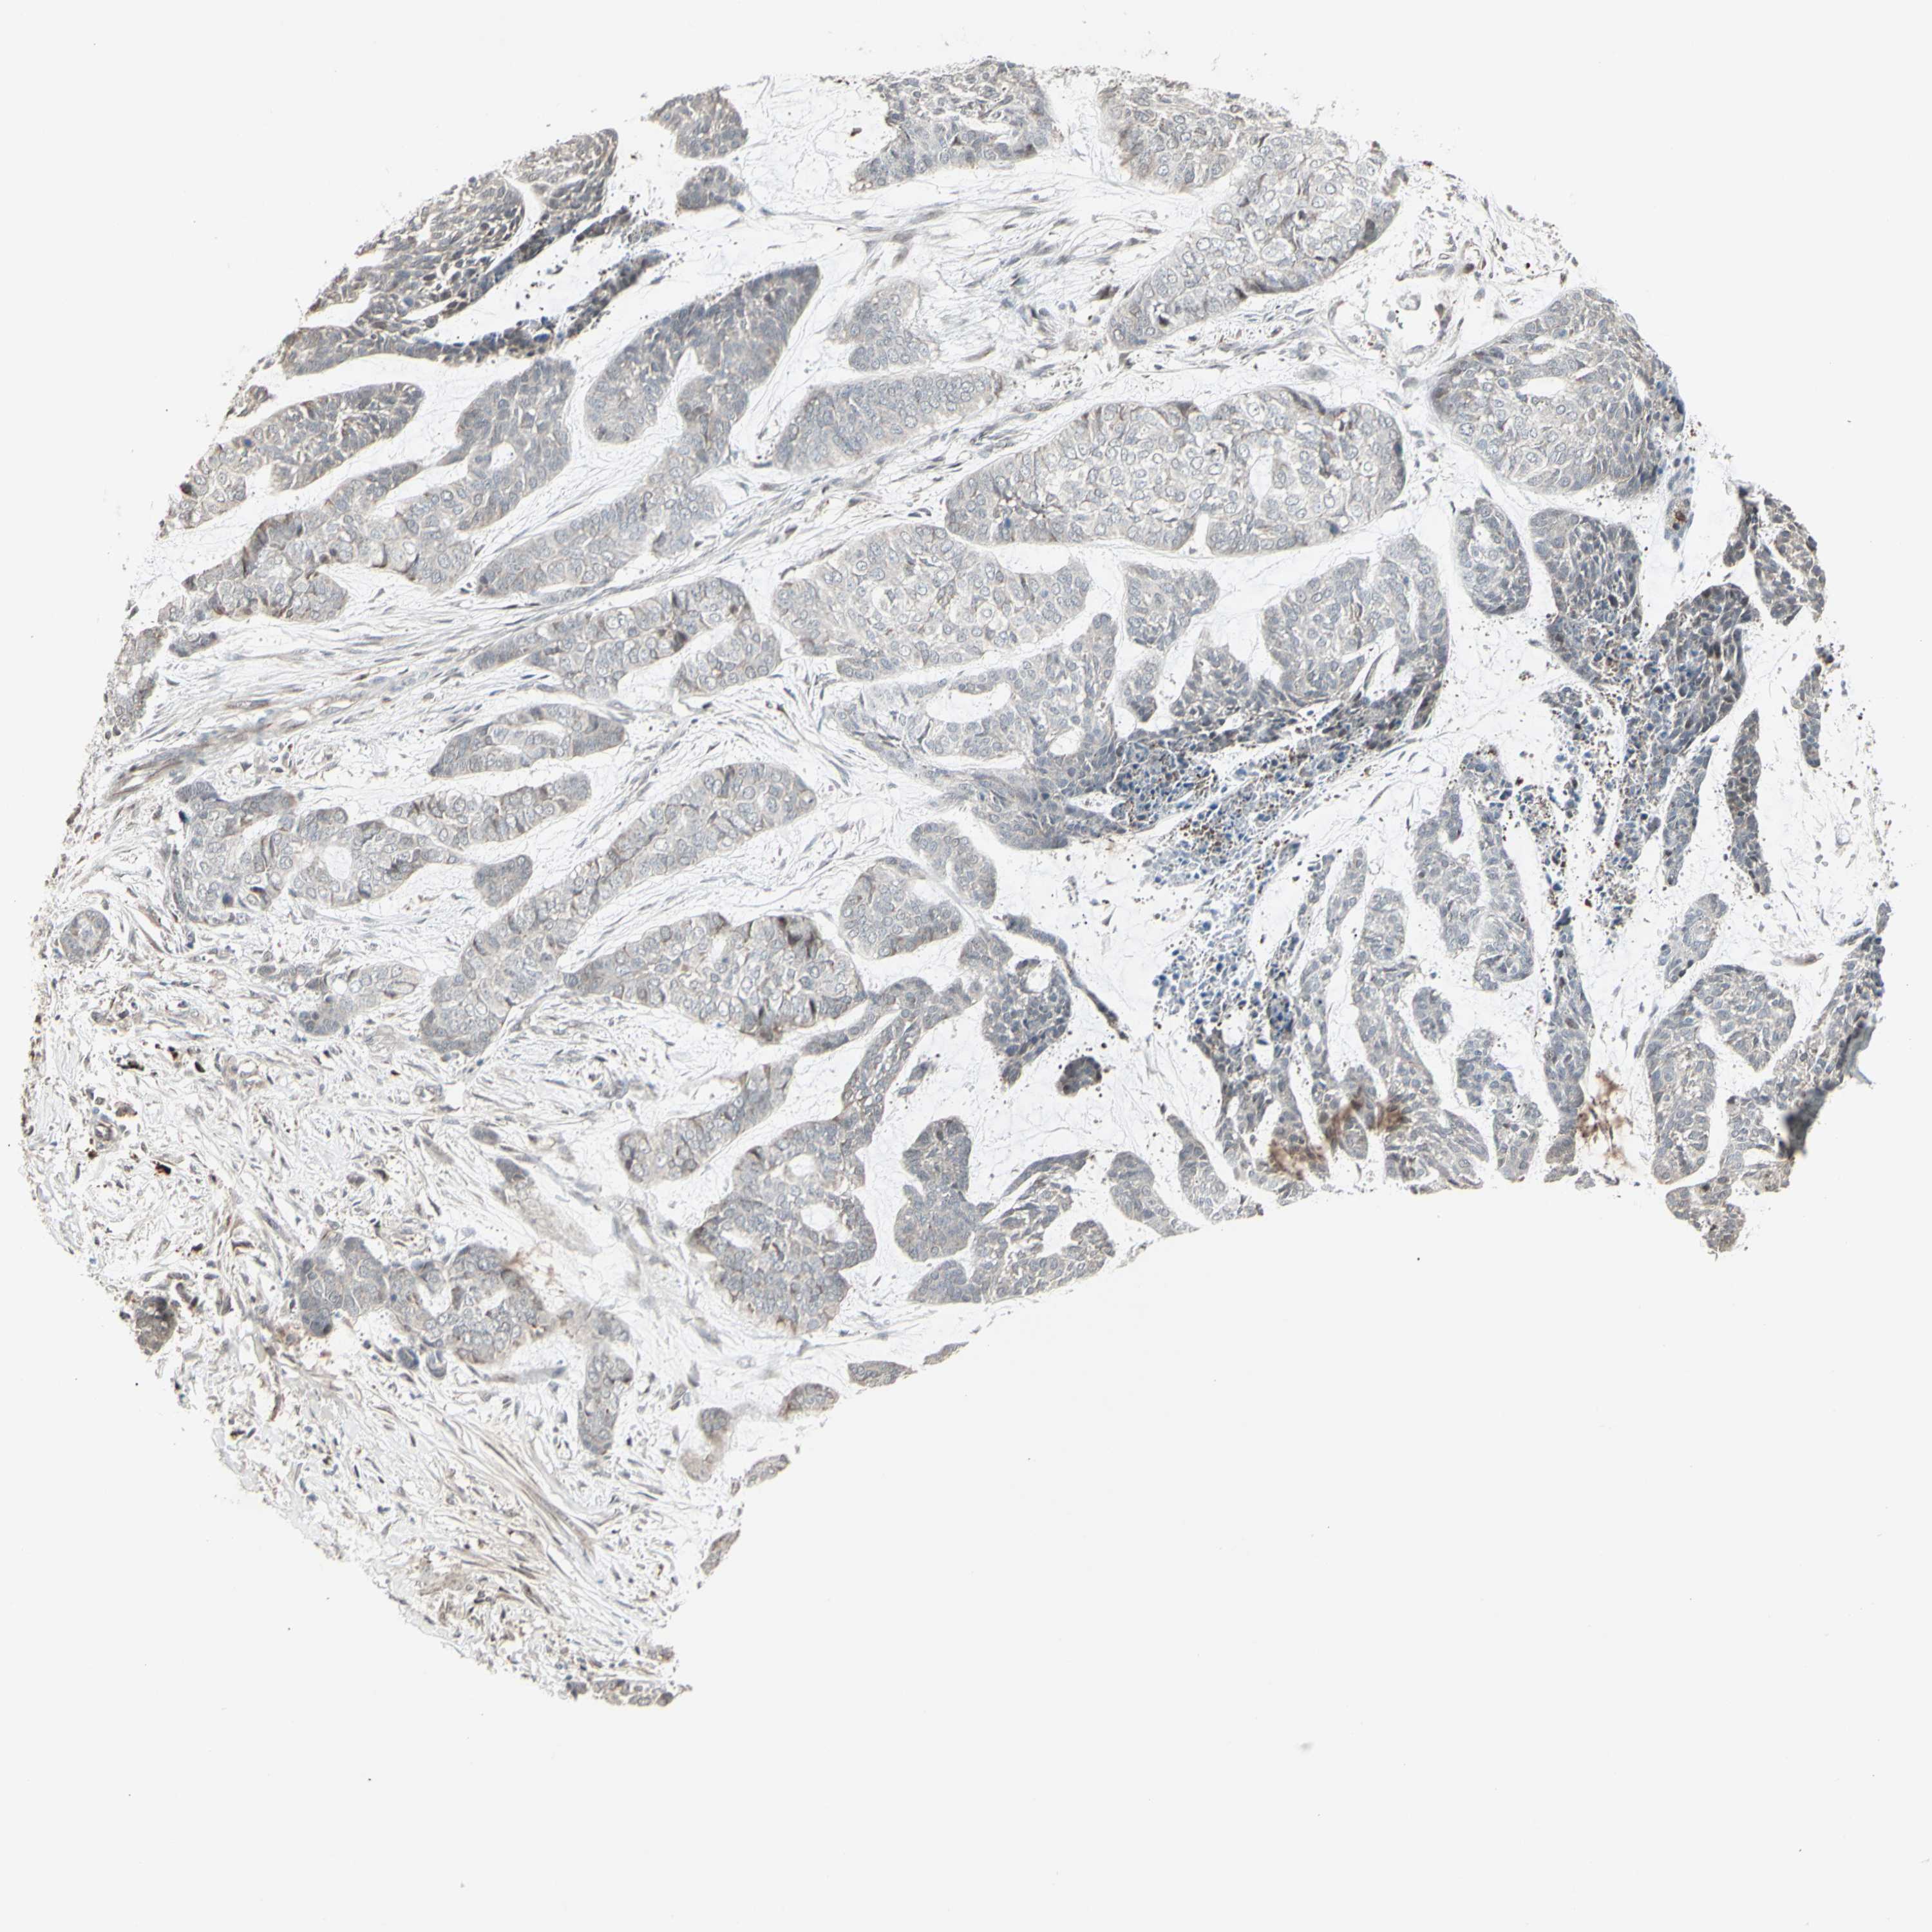

Basal cell and squamous cell cancer

SKIN CANCER - Protein expressioni

A mouse-over function shows sample information and annotation data. Click on an image to view it in a full screen mode. Samples can be filtered based on level of antibody staining by selecting one or several of the following categories: high, medium, low and not detected. The assay and annotation is described here.

Antibody stainingi

Antibody staining in the annotated cell types in the current human tissue is reported as not detected, low, medium, or high, based on conventional immunohistochemistry profiling in selected tissues. This score is based on the combination of the staining intensity and fraction of stained cells.

Each image is clickable and will lead to virtual microscopy that enables deeper exploration of all samples and also displays staining intensity scores, fraction scores and subcellular localization as well as patient and tissue information for each sample.

Antibody HPA035832

Basal cell carcinoma

Squamous cell carcinoma, NOS

Squamous cell carcinoma, metastatic, NOS

Papilloma, NOS